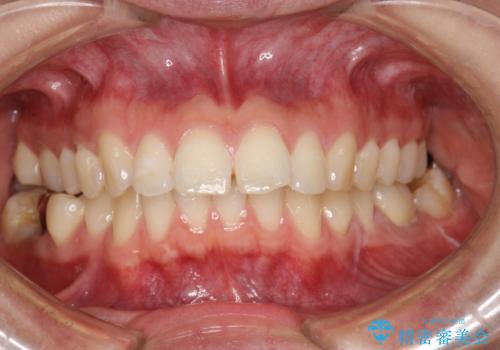

見た目もよくなり、口も閉じるようになったと満足していただけました。

予定よりも早く終了することができたことにも喜んでいただけました。